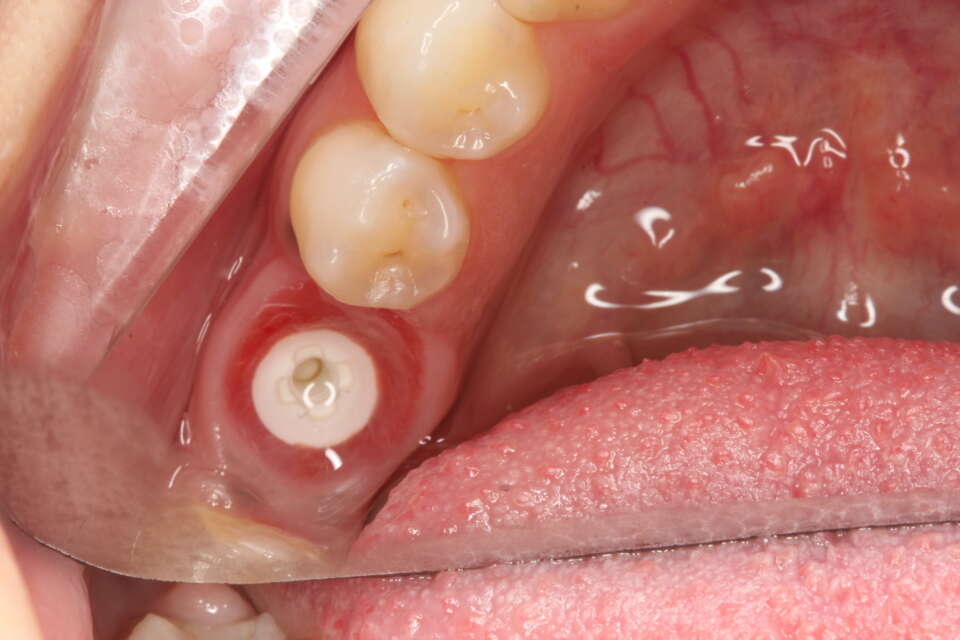

Zirconia Dental Implant in Situ

IMG 8704

Zirconia dental implant after healing. Note how the implant is white in colour compared to titanium which is grey.